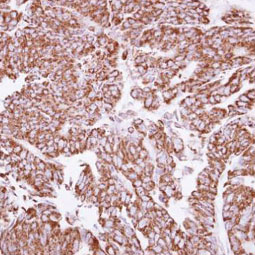

![TIE1 antibody [12D9] (GTX52470)](/upload/media/research/Cancer/Angiogenesis/5.jpg)

![TIE2 antibody [21G7] (GTX52471)](/upload/media/research/Cancer/Angiogenesis/6.jpg)